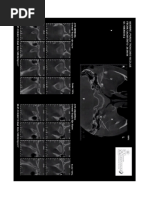

Radiografía de la ATM

Radiografías de ATM en posición de boca

cerrada (A) y boca abierta (B).

Se señalan las diferentes partes anatómicas:

1. Fosa temporal

2. Conducto auditivo externo

3. Hueso cigomático

4. Cóndilo del temporal

5. Cavidad glenoidea (lugar donde se

alojará el cóndilo mandibular)

6. Apófisis estiloide del hueso temporal

7. Cóndilo mandibular

8. Espacio faríngeo